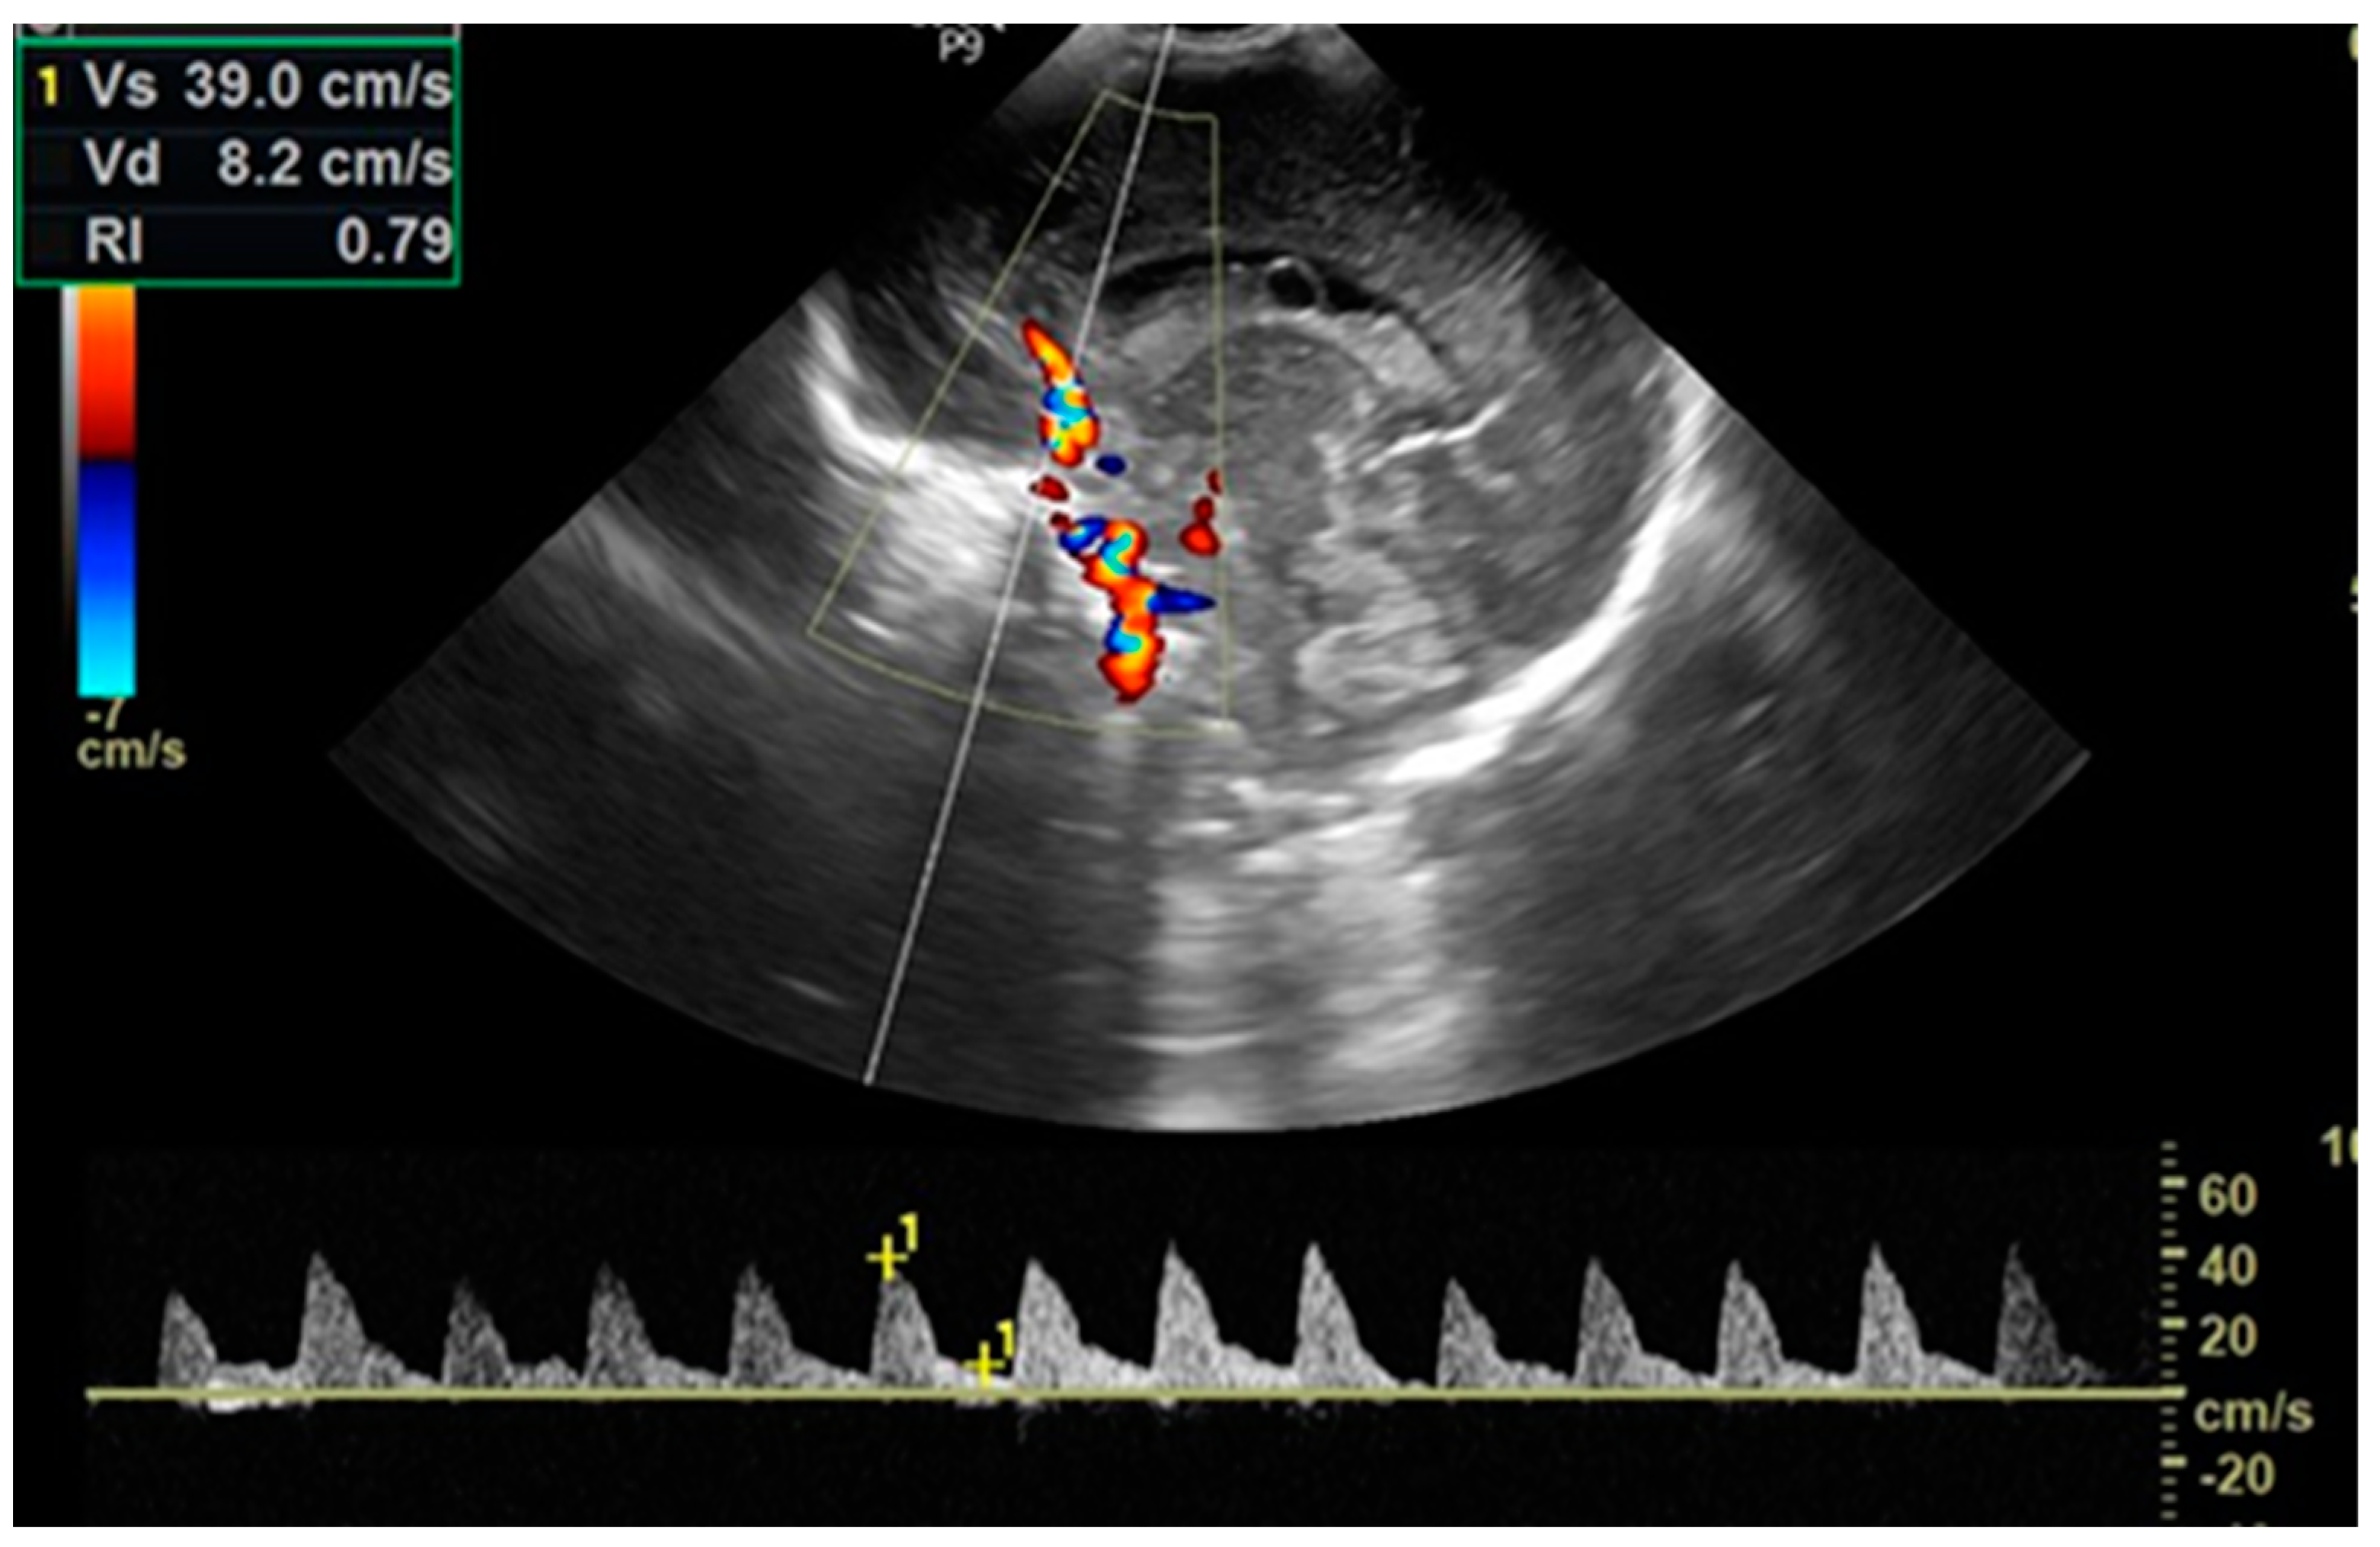

| RI §, mean (SD) | ||||||

| within 2 h of life (before PGE1) | 0.718 (0.054) | 0.708 (0.054) | 0.713 (0.05) | 0.3990 | 0.6812 | 0.5761 |

| before BAS | 0.759 (0.046) | |||||

| 24 h of life | 0.769 (0.036) | 0.764 (0.041) | 0.681 (0.046) | 0.6272 | 0.00002 * | 0.00002 * |

| PSV §, (cm/s), mean (SD) | ||||||

| within 2 h of life (before PGE1) | 39.75 (7.41) | 37.78 (7.82) | 34.49 (6.71) | 0.4177 | 0.0007 * | 0.03831 |

| before BAS | 40.41 (8.92) | |||||

| 24 h of life | 38.99 (5.29) | 39.72 (6.53) | 37.35 (7.80) | 0.8958 | 0.5651 | 0.2313 |

| EDV §, (cm/s), mean (SD) | ||||||

| within 2 h of life (before PGE1) | 10.71 (1.61) | 10.86 (2.54) | 9.78 (2.01) | 0.7171 | 0.0292 * | 0.0153 * |

| before BAS | 9.27 (1.91) | |||||

| 24 h of life | 8.74 (1.31) | 9.16 (2.00) | 11.83 (2.39) | 0.687 | 0.00001 * | 0.00002 * |